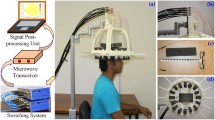

Microwave based head investigation has recently attracted a huge attention as a non-invasive alternative or complementary non-ionizing diagnostic tool for various biomedical applications15,16,17,18,19,20,21. This work reports a portable microwave head imaging system, which is simple to employ and consists of an imaging platform, a compactly designed ultra-wideband (UWB) antenna22, a microwave transceiver and a data storing and processing unit. The presented head imaging system utilizes radar based back projection algorithm based on effective permittivity model. One of the prime disadvantages of existing radar based algorithms is the presumption of a constant value for the effective permittivity of the imaged body in order to map the head for any significant scatterer21,23,24,25. However, using a constant number for the heterogeneous head that has various tissues leads to significant imaging errors that may lead to incorrect detection and localization26,27. To address this problem, several researchers have utilized the estimation of direct time of flight of the signal through the imaged body28 or time-domain inverse scattering technique that estimates the spatially averaged permittivity29. However, in a multipath environment such as the heterogeneous human head, the penetrating signal faces different tissues with wide range of properties and thicknesses. In this work, a novel location-dependent point-of-entry based effective head permittivity model derived using the numerical analysis of a healthy human head is proposed. An improved delay-and-sum (DAS) algorithm relying on the derived permittivity model is then employed for reconstructing an image of the head interior with enhanced detection accuracy. The system and algorithm are validated in realistic simulation and experimental environment by using anatomically realistic three-dimensional (3D) printed human head phantom. The radiation and thermal safety of the system are also verified. Human trials on healthy volunteers are then conducted to determinate the type, statistics and thresholds of obtained images as a necessary step for future preclinical trials.

The architecture of the experimental head imaging system is illustrated in Fig. 1(a). The system primarily consists of a compact antenna to transmit and receive wideband signals, a microwave transceiver for signal generation and data acquisition and a personal computer for signal processing and image formation. A head imaging platform is designed to evaluate the system’s performance on detecting ICH using a realistic head phantom. During image, the head phantom is placed at the rotatable platform and scanned using the wideband antenna, which is mounted on an adjustable antenna holder.

A prototype of the head imaging system is developed in order to test on healthy volunteers. The prototype is equivalent to the system illustrated in Fig. 1(a). The experimental protocols are approved by the Medical Research Ethics Committee (MREC) and Behavioural and Social Sciences Ethical Review Committee (BSSERC) of The University of Queensland for research involving human participants. The experiments on volunteers are performed in accordance with the relevant guidelines and regulations approved by the ethical committees. The participation of the volunteers is maintained in accordance to the approved guidelines and informed consents are obtained from the volunteers. At the time of experiment, the volunteer sits on an angle controllable seat, facing the antenna and the adjustable antenna holder. The antenna is connected with the microwave transceiver and data processing computer. A 15 mm foam spacer is used in order to fix the distance of the antenna from the volunteer’s head. The backrest of the chair provides support to the volunteer’s back and holds the head in a reasonably fixed position. A light reference head band is utilized to follow-up the investigation plane. As each volunteer has different head appearances, the shape and size of the head is also measured by assessing the reference head band plane. The total power transmitted by the prototype system is 0 dBm. The data from the head of the volunteer are acquired in 1–2 minutes from various angles around the head. The data is then stored and analysed by using the proposed algorithm based on the model of effective head permittivity. The results of the healthy volunteers are presented in Fig. 7.